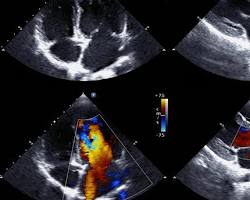

- Ecocardiografia: Această examinare utilizează ultrasunete pentru a obține imagini ale inimii în mișcare, permițând evaluarea structurii și funcției cardiace.Echocardiography